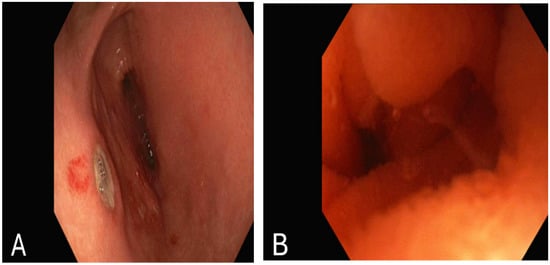

The patient was diagnosed with a duodenal hematoma, and surgical intervention was discussed with the surgical team. However, due to the patient’s stable condition, the surgeon recommended continuing with medical management. By the third day, her symptoms, including vomiting and abdominal pain, had improved. It was recommended to continue NPO with an NG tube. An esophagogastroduodenoscopy (EGD) was performed, revealing several non-bleeding gastric ulcers in the gastric antrum, likely secondary to NG tube trauma (Figure 2A). Additionally, severe acquired extrinsic stenosis was observed in the second portion of the duodenum (Figure 2B).

Figure 2. Esophagogastroduodenoscopy showing: (A): several non-bleeding gastric ulcers in the gastric antrum. (B): stenosis in the second part of the duodenum.